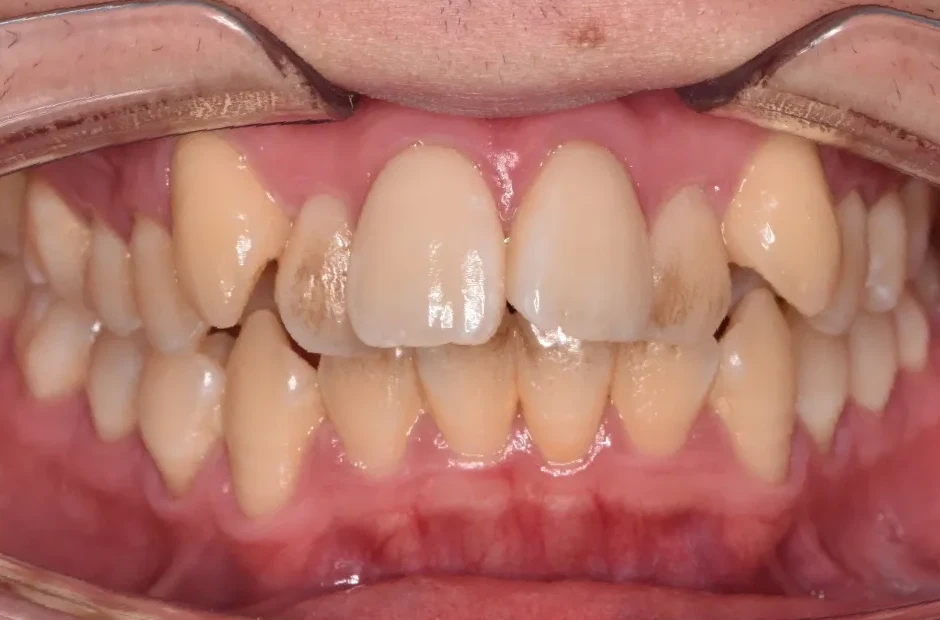

治療前